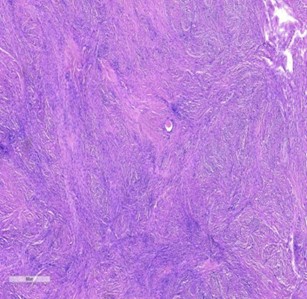

Figure 4. Micrograph showing the leiomyoma composed of interlacing fascicles of smooth muscle cells and interspersed blood vessels X40 magnification.